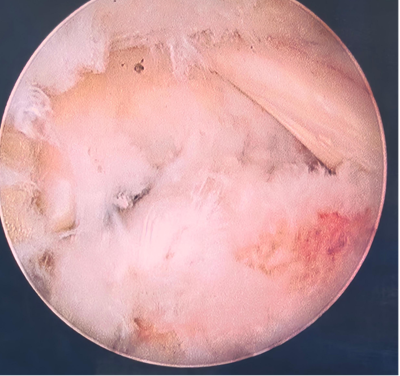

后踝关节镜下显露距后三角骨